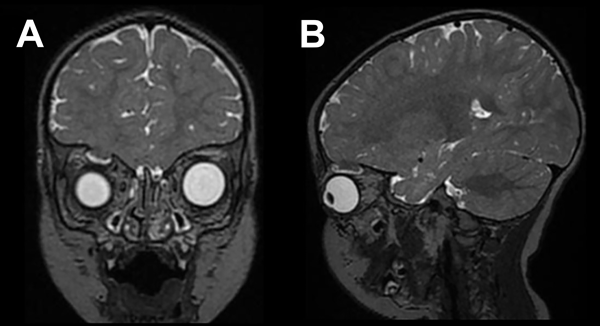

El paciente no presentó déficits neurológicos y se mantuvo en observación por 48 horas, para luego ser dado de alta. Durante el seguimiento ambulatorio, a los 3 meses del TEC, se detectó en el examen físico ptosis palpebral, distopía vertical y debilidad en la musculatura extrínseca ocular derecha. Se realizó RM y TC de encéfalo con reconstrucción tridimensional, en estas se evidenció ensanchamiento del trazo fracturado con diástasis ósea y herniación de estructuras encefálicas a través de este, hacia la cavidad orbitaria (Figuras 2 y 3). Se determinó la necesidad del tratamiento neuroquirúrgico para la reparación del defecto, se efectuaron estudios prequirúrgicos de rutina, previos a la intervención.

Figura 2. TC de encéfalo. A) Ventana ósea corte coronal. B) Ventana ósea corte sagital. C y D) Reconstrucción 3D. Se observa diástasis ósea, con bordes óseos redondeados.

Figura 3. RM de encéfalo. A) Corte coronal. B) Corte sagital ponderado en secuencia T2 en la que se visualiza herniación de parénquima y LCR hacia la cavidad orbitaria.